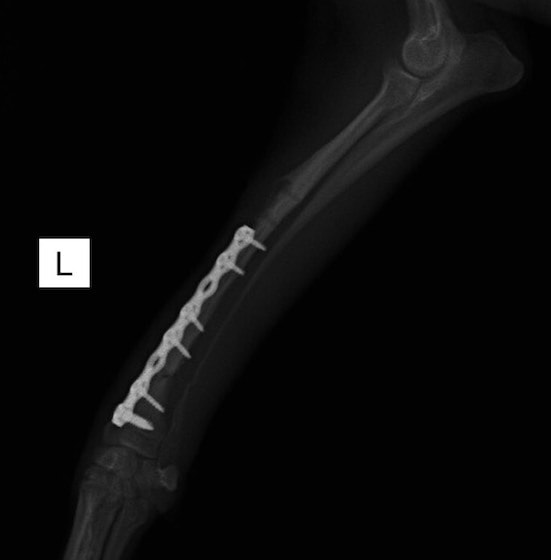

症例3:キルシュナーワイヤーのピンニングによる整復

ペルシャ猫 11ヶ月齢 雄

他院にて左大腿骨遠位の成長板骨折(salter-harrisⅠ型)が認められており、治療相談を目的として来院。当院にて、キルシュナーワイヤーを用いたピンニングにより骨折部位の整復を行いました。術後の経過は良好で、現在も経過観察中です。

術前レントゲン

術後レントゲン

機器

Arthrex社のターゲティングデバイスを用いてピンニングの位置を調整することで、確実な固定を行っています。当院ではこの手術器具以外にも、人の手術にも使用される様々な器具を導入し、手術精度を高め、また医療メーカーと新しい器具の開発、試作にも取り組んでおります。